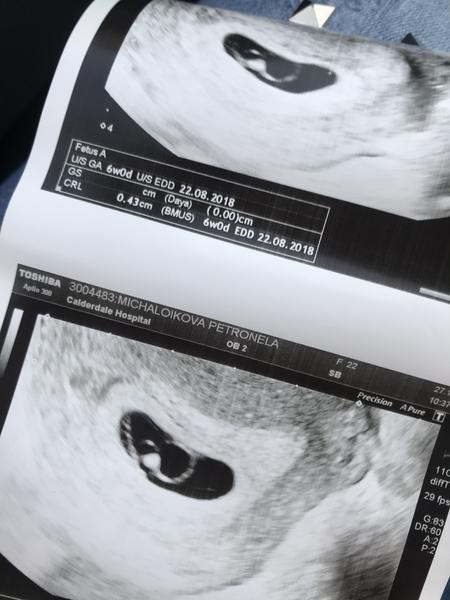

Zdravim...dnes som bola na ultrazvuku ( prikladam fotku ) som v 7tt

Sestricka si nieje ista ci .. cakam

Jedno alebo dve... baba

Len koli tomu ze bolo vydno este jedno take mensie kruzko .. ak vidite co myslim ....

Co je vidiet teda v 7tt na ultrazvuku co tym myslela pupocna snura zeny boli dve ? A uz je vidiet ? Alebo teda ten gestacny vacok ??

@nellynnnka gratulujem. Inak mne každý podľa fotky hovoril, že čakám dve...ale skutočne len jedno a aj jedno srdiečko bilo ❤️

@nellynnnka aj mne lekár vravel ze niektorý doktor by povedal ze budem mat dvojčatka lebo si niekedy mýlia zltkovy vak s bábom 😉